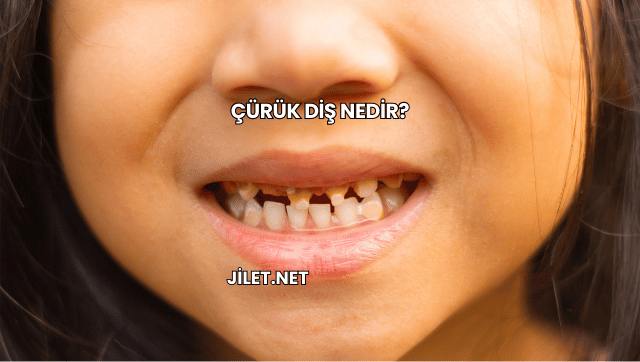

Çürük diş, diş minesinin asit üreten ağız bakterileri tarafından zamanla aşındırılması sonucu oluşan yaygın bir sorun olup erken dönemde tespit edilmediğinde sinir dokusuna kadar ilerleyerek şiddetli ağrı ve enfeksiyonlara yol açabilir. Bu yazıda çürük dişin tanımı, nedenleri, belirtileri, tedavi yöntemleri ve koruyucu önlemler ele alınarak kapsamlı bir bakış açısı sunuluyor.

Çürük diş, diş yüzeyindeki plakların asit salınımıyla mine dokusunu zayıflatması sonucu oluşur ve şekerli gıdaların tüketimi, yetersiz ağız hijyeni ile birleştiğinde diş yapısındaki mineral kaybını hızlandırarak çürüme sürecini tetikler.

Çürük diş, genellikle erken evrede belirti vermese de mine tabakasında zayıflama başladığında ağrı, hassasiyet ve renk değişiklikleriyle kendini gösterir.

Çürük alanları diş yüzeyinde kahverengi veya siyah lekeler oluşturabilir ve ışık altında mat görünümle ayrışır.